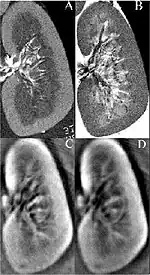

Thermoacoustic imaging was originally proposed by Theodore Bowen in 1981 as a strategy for studying the absorption properties of human tissue using virtually any kind of electromagnetic radiation.[1] But Alexander Graham Bell first reported the physical principle upon which thermoacoustic imaging is based a century earlier.[2] He observed that audible sound could be created by illuminating an intermittent beam of sunlight onto a rubber sheet. Shortly after Bowen's work was published, other researchers proposed methodology for thermoacoustic imaging using microwaves.[3] In 1994 researchers used an infrared laser to produce the first thermoacoustic images of near-infrared optical absorption in a tissue-mimicking phantom, albeit in two dimensions (2D).[4] In 1995 other researchers formulated a general reconstruction algorithm by which 2D thermoacoustic images could be computed from their "projections," i.e. thermoacoustic computed tomography (TCT).[5] By 1998 researchers at Indiana University Medical Center[6] extended TCT to 3D and employed pulsed microwaves to produce the first fully three-dimensional (3D) thermoacoustic images of biologic tissue [an excised lamb kidney (Fig. 1)].[7] The following year they created the first fully 3D thermoacoustic images of cancer in the human breast, again using pulsed microwaves (Fig. 2).[8] Since that time, thermoacoustic imaging has gained widespread popularity in research institutions worldwide.[9][10][11][12][13][14][15] As of 2008, three companies were developing commercial thermoacoustic imaging systems – Seno Medical,[16] Endra, Inc.[17] and OptoSonics, Inc.[18]